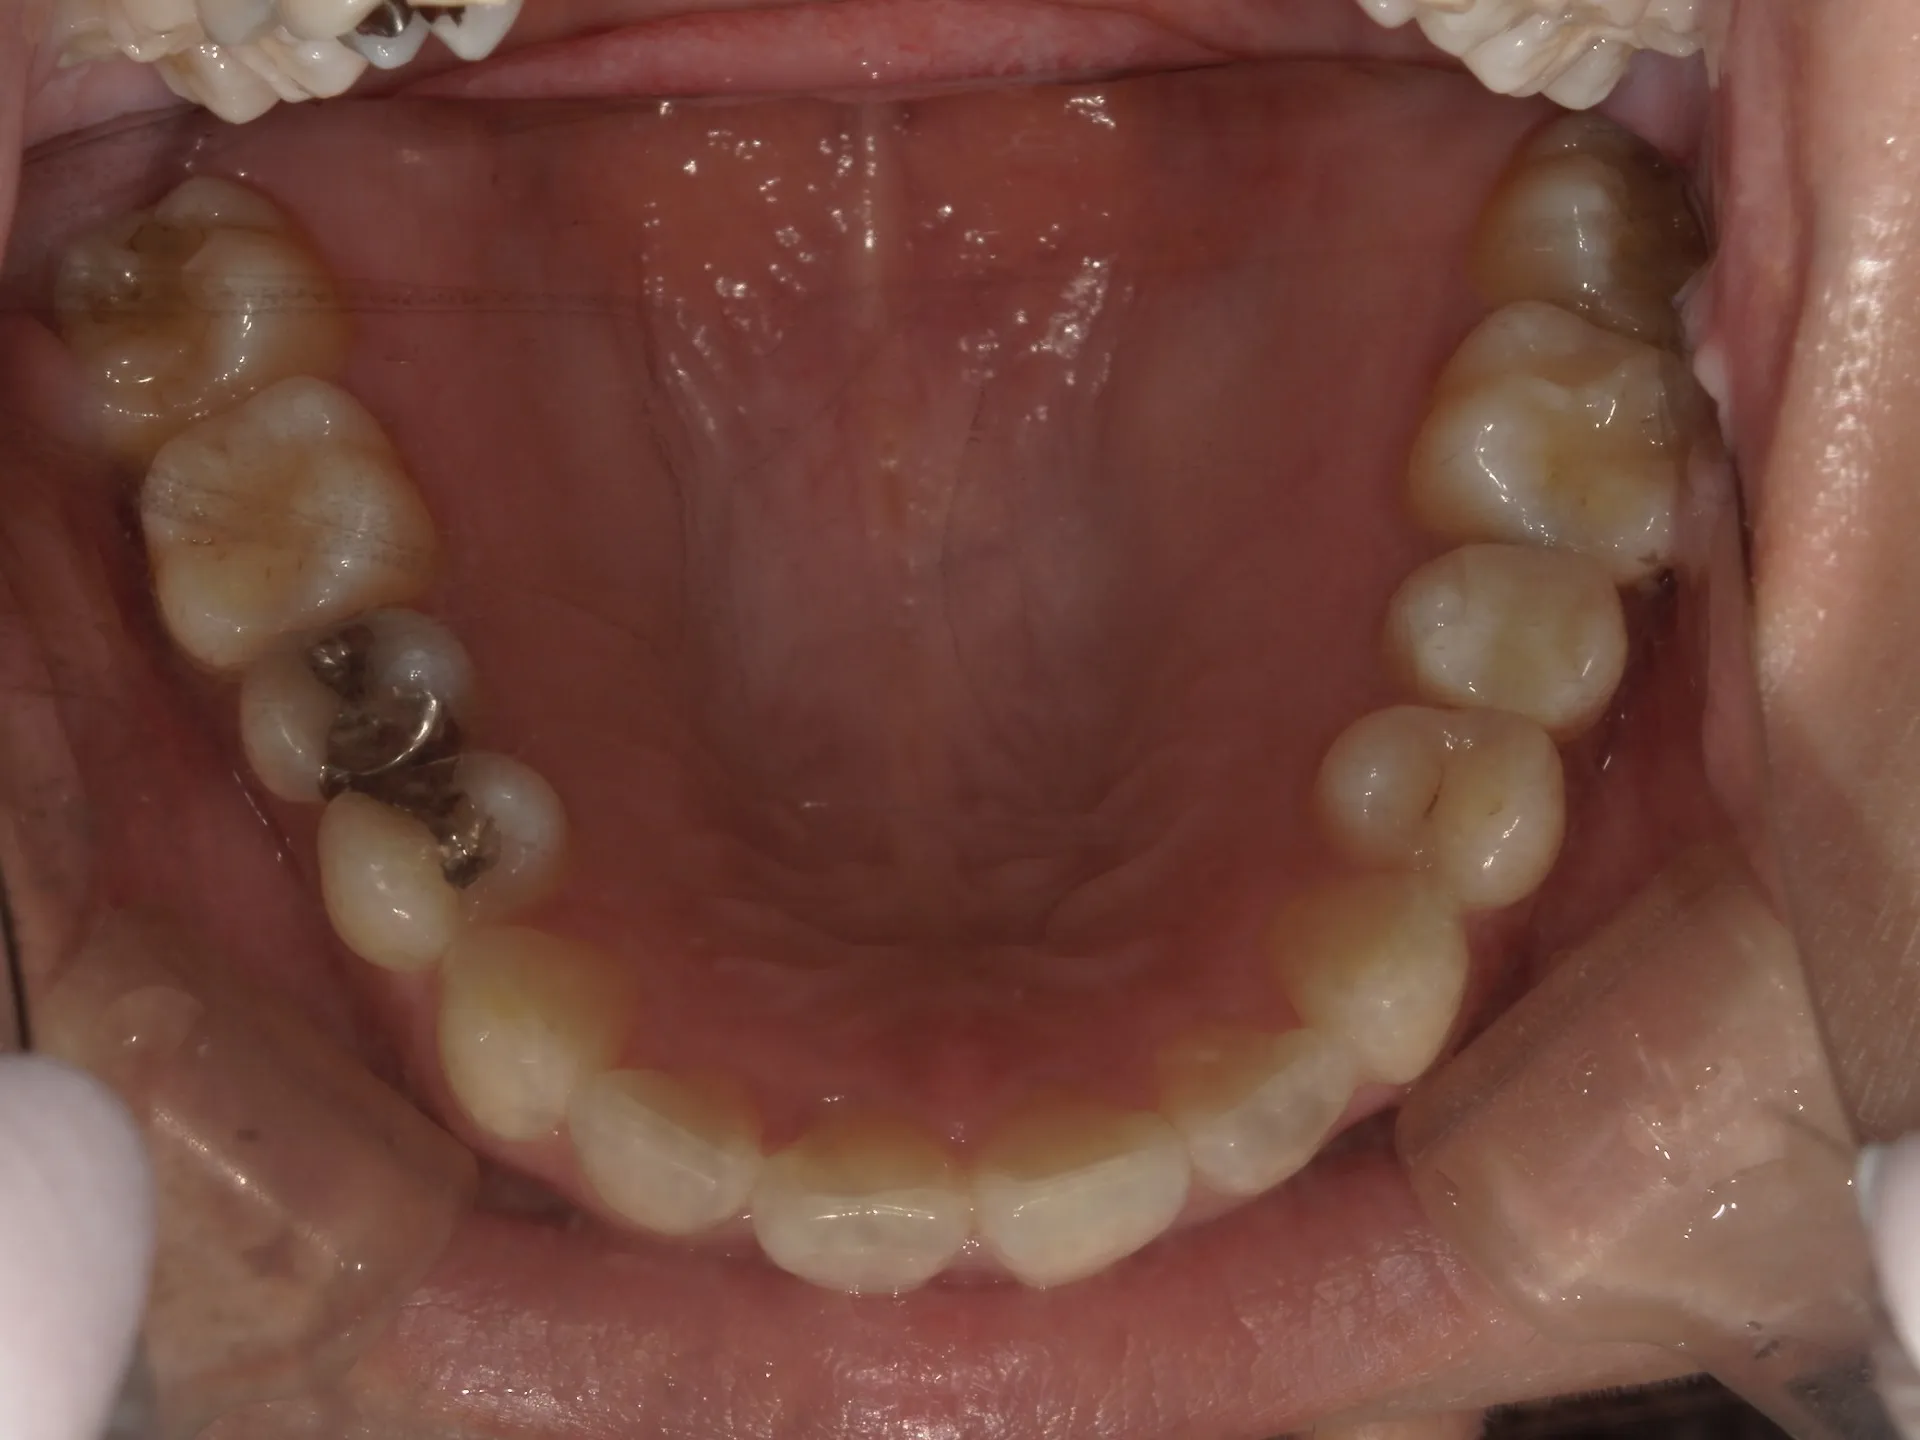

正面観

初診時

上の前歯が1本大きくねじれ、更にその歯に変色も見られました。

下の歯もスペースがなくガタついている状態の歯並びでした。